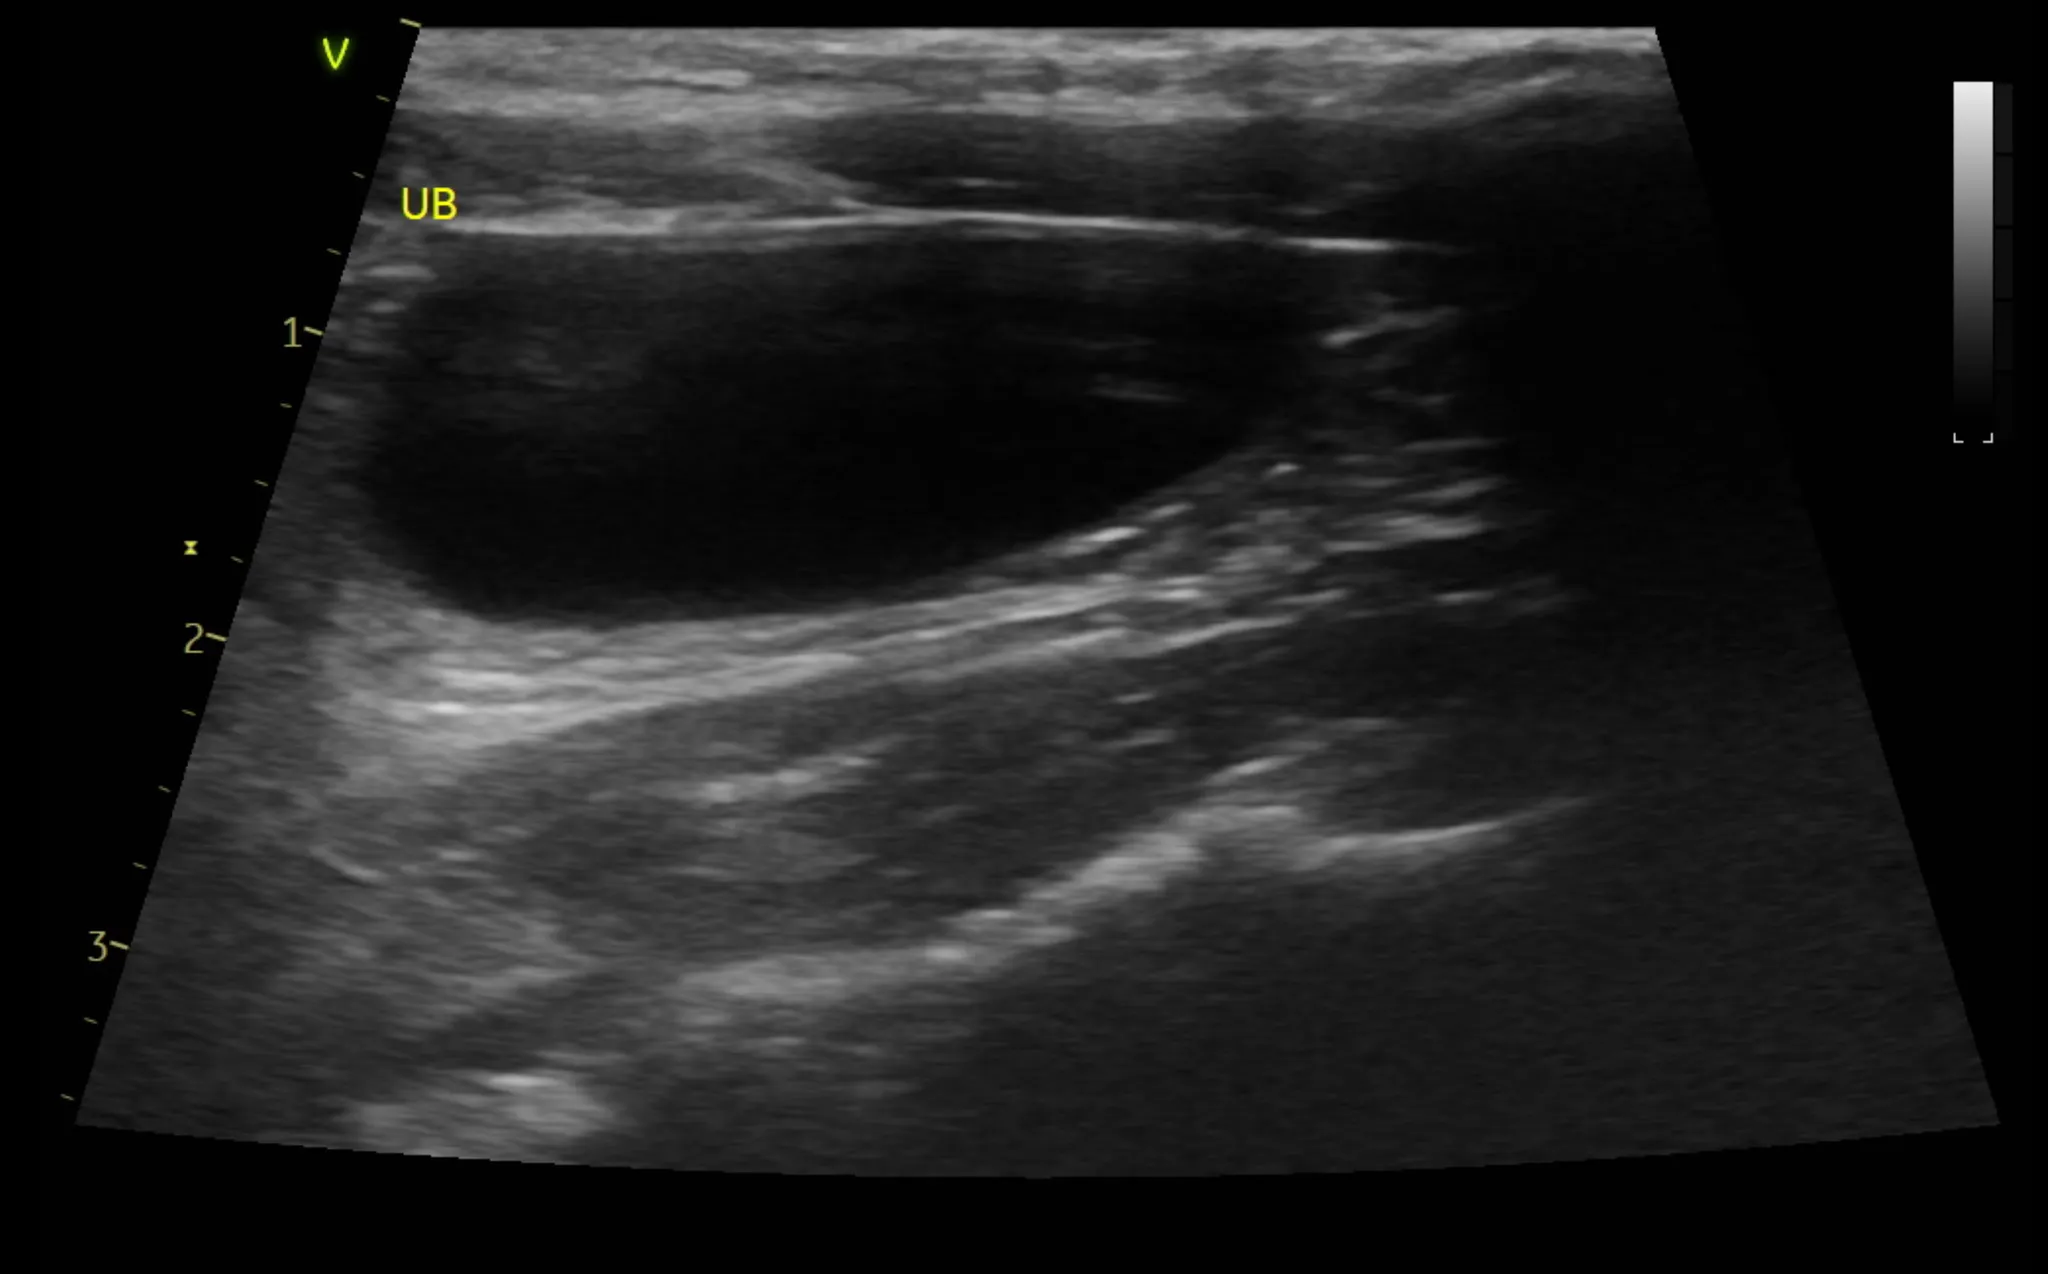

3. 복부 초음파 검사 결과

복부 초음파 검사로는 간, 신장 등 복부 장기의 모양과 결석, 종양등의 이상여부를 알 수 있습니다.

또한 방광 결석, 다낭포성 신장질환 같은 고양이에서 잘 생기는 질환의 경우 초음파 검사로만 알 수 있으므로 매우 중요한 검사 중 하나입니다.

•

복부 초음파 검사 상 특이사항은 발견되지 않았습니다.

1년 주기로 검사를 추천드립니다.